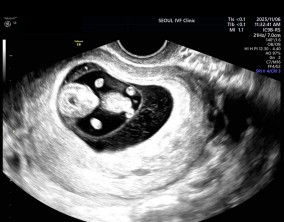

설렘과 불안의 시간을 지나 찾아온 선물

서울IVF여성의원의 난임 치료는 과정 하나하나가 체계적이고 세심하다는 인상을 받았습니다. 이유정 원장님과 간호사 분들께 치료 단계마다 충분한 설명을 들을 수 있어 불안이 많…